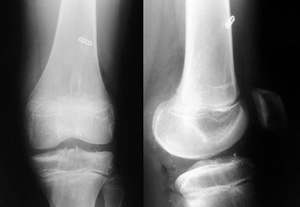

Las técnicas transfisiarias convencionales son la que mejor restablecen la estabilidad de la rodilla logrando una colocación anatómica de los túneles. (19) El uso de técnicas transfisiarias se prefiere en paciente en estadio III de Tanner en adelante, en que el crecimiento restante de la fisis tibial y femoral es limitado. Se ha publicado el uso de estas técnicas en pacientes menores. Streich et al (20) reportó el uso de técnicas transfisiarias en 12 pacientes en estadio de Tanner 1 y 2, con edades entre 9 y 12 años, con un seguimiento de 70 meses en que no observó deformidades angulares ni discrepancia de longitud. El temor al daño de la fisis por el procedimiento quirúrgico ha sido estudiado en animales. Los resultados sugieren un túnel transfisiario que comprometa el 9% de la superficie fisiaria central y se rellene con tejido de partes blandas que no permita el crecimiento óseo, no causa epifisiodesis temprana ni deformaciones angulares. Existen ciertas consideraciones técnicas que se deben tener en cuenta al momento de la técnica transfisiaria para disminuir el riesgo de efectos iatrogénicos, como son: elección de injerto, posición de los túneles y fijación (Figs. 2 y 3).

| Figura 2: Técnica quirúrgica de la reconstrucción LCA transfisiaria. El túnel debe ser en posición más vertical de ancho 7 mm, con fijaciones alejadas de la fisis y túnel completamente relleno con injerto. | Figura 3: Errores de la técnica quirúrgica, colocación de tonillos interferenciales a través de la fisis. |

Los implantes contraindicados en pacientes con esqueleto inmaduro son tornillos interferenciales, ya sea metálicos o reabsorbibles que queden ubicados a través de la fisis dentro del túnel (16) (Fig. 4).

Figura 4: Radiografías post operatorias de paciente de 11 años (fisis abierta) en que se realizó reconstrucción transfisiaria del LCA. Se utilizó túneles pequeños verticales y fijaciones alejadas de la fisis.